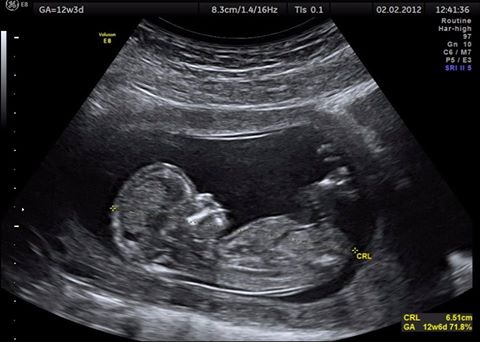

In October, Blue Water Grill (BWG), together with The Phoenix and Wine de Vine, will be holding their monthly donation drive for a grand project: an ultrasound machine for the Dr. Otto Rodriguez San Pedro Polyclinic II. Many community members cannot afford to visit a private clinic, and according to BWG, this could result in many negative outcomes, particularly for women seeking prenatal care.

Since Dr. Otto Rodriguez San Pedro Polyclinic II does not have an ultrasound machine, and it costs $32,000 to obtain one, these three businesses will be pledging the initial $16,000. BWG is hoping to receive a matching amount in donations in order to purchase an ultrasound machine for the clinic. If the goal is not met in October, BWG will continue the effort in November.